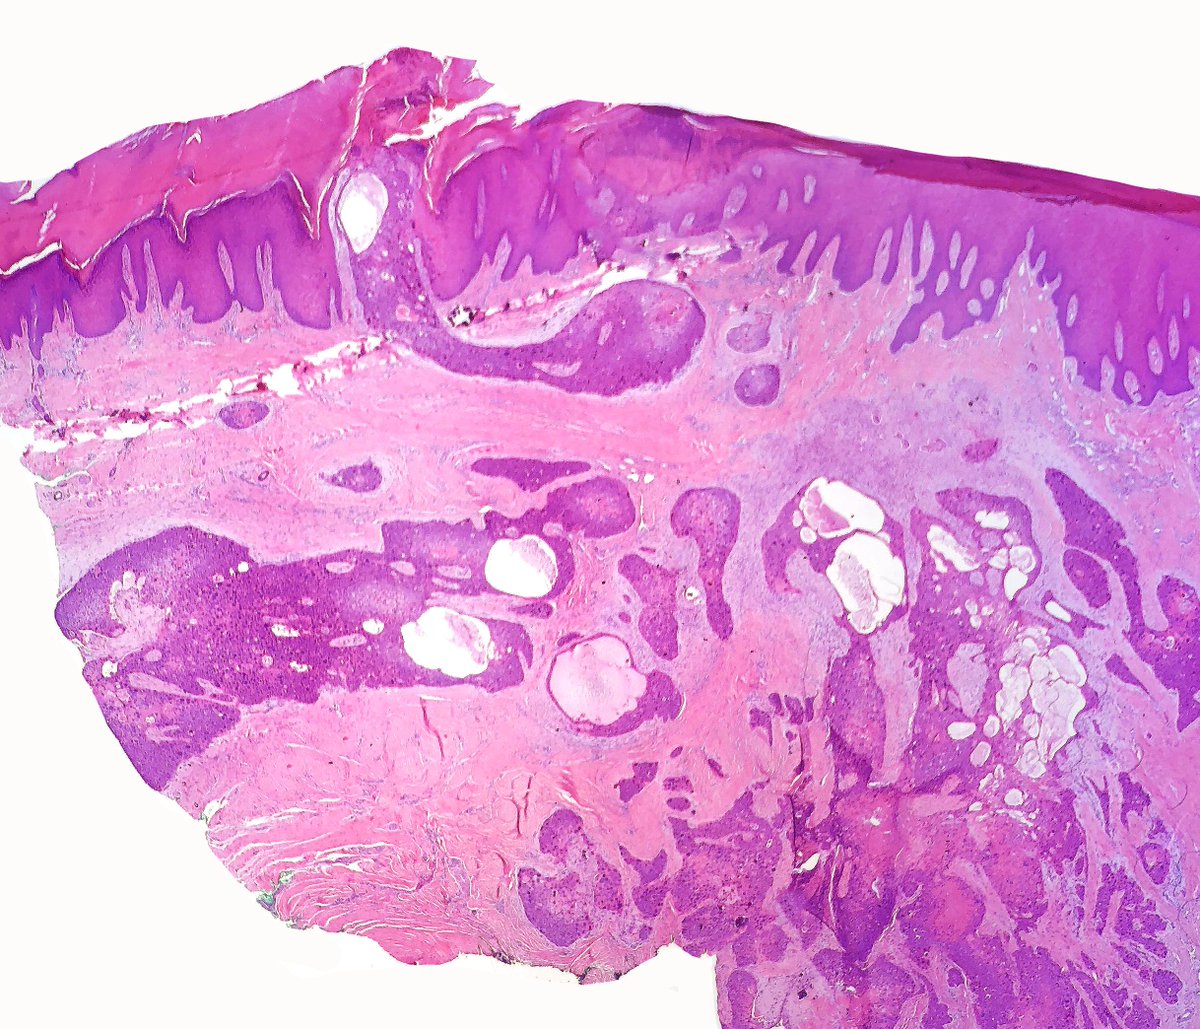

Elderly man, foot mass. Previous superficial shave biopsy called SCCIS. This is the excision. #dermpath